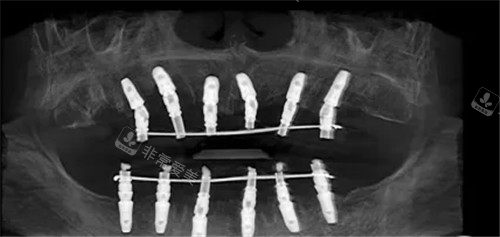

全口种植ct图片